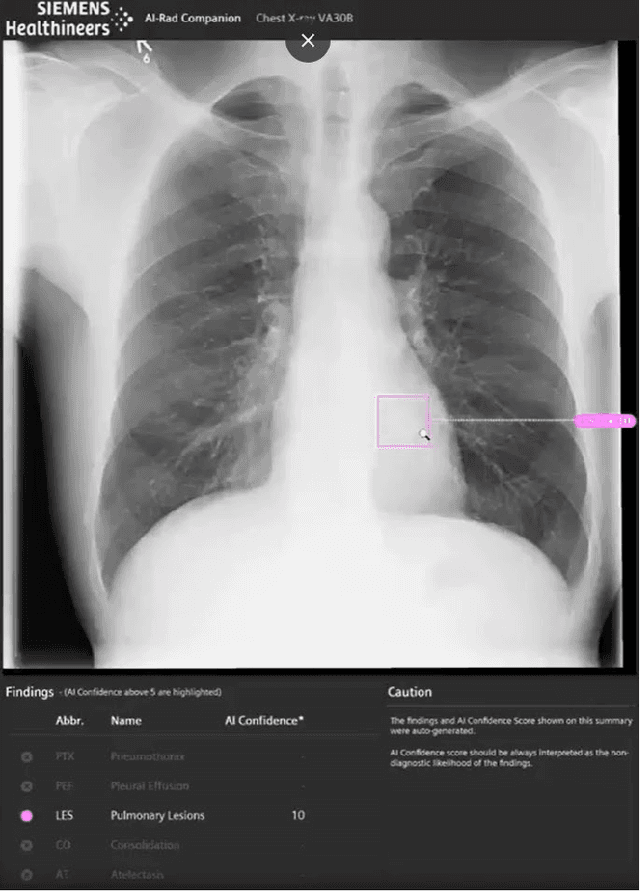

Abstract:Research question: How can we establish an AI support for reading of chest X-rays in clinical routine and which benefits emerge for the clinicians and radiologists. Can it perform 24/7 support for practicing clinicians? 2. Findings: We installed an AI solution for Chest X-ray in a given structure (MVZ Uhlenbrock & Partner, Germany). We could demonstrate the practicability, performance, and benefits in 10 connected clinical sites. 3. Meaning: A commercially available AI solution for the evaluation of Chest X-ray images is able to help radiologists and clinical colleagues 24/7 in a complex environment. The system performs in a robust manner, supporting radiologists and clinical colleagues in their important decisions, in practises and hospitals regardless of the user and X-ray system type producing the image-data.